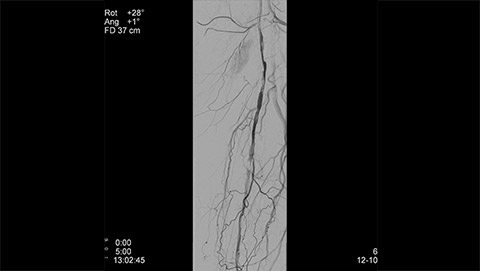

Whether treating critical limb ischemia, embolizing an uterine fibroid, or performing a biopsy or Endovascular Aneurysm Repair (EVAR) procedure, speed, clarity, and efficient dose management are key. Our multimodality Live Image Guidance solutions deliver critical information to optimize real-time guidance through complex vasculature and visualize tissue perfusion to identify treatment end-point in peripheral vascular interventions. At the same time, our AlluraClarity family with ClarityIQ technology enables physicians to deliver fast, effective, and simplified procedures with an efficient clinical workflow. All while delivering equivalent image quality at a fraction of the dose Sign up to receive exclusive updates on Live Image Guidance.

Dynamic 3D Roadmap provides a sustainable 3D roadmap to support interventional procedures. Dynamic 3D Roadmap matches the real-time 2D fluoroscopy images with the 3D-RA reconstruction of the vessel tree. It provides a 3D real-time insight of the advancement of the guide wire, catheter and coils through complex vessel structures. The Unsubtracted 3D Roadmap option reduces subtraction artifacts caused by patient breathing and movements, providing a clear roadmap during abdominal and thoracic interventions.